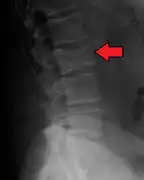

The diagnostic examination of a person with suspected multiple myeloma typically includes a skeletal survey. This is a series of X-rays of the skull, axial skeleton, and proximal long bones. Myeloma activity sometimes appears as "lytic lesions" (with local disappearance of normal bone due to resorption). And on the skull X-ray as "punched-out lesions" (pepper-pot skull). Lesions may also be sclerotic, which is seen as radiodense.[47] Overall, the radiodensity of myeloma is between −30 and 120 Hounsfield units (HU).[48] Magnetic resonance imaging is more sensitive than simple X-rays in the detection of lytic lesions, and may supersede a skeletal survey, especially when vertebral disease is suspected. Occasionally, a CT scan is performed to measure the size of soft-tissue plasmacytomas. Bone scans are typically not of any additional value in the workup of people with myeloma (no new bone formation; lytic lesions not well visualized on bone scan).

Pathological fracture of the lumbar spine due to multiple myeloma